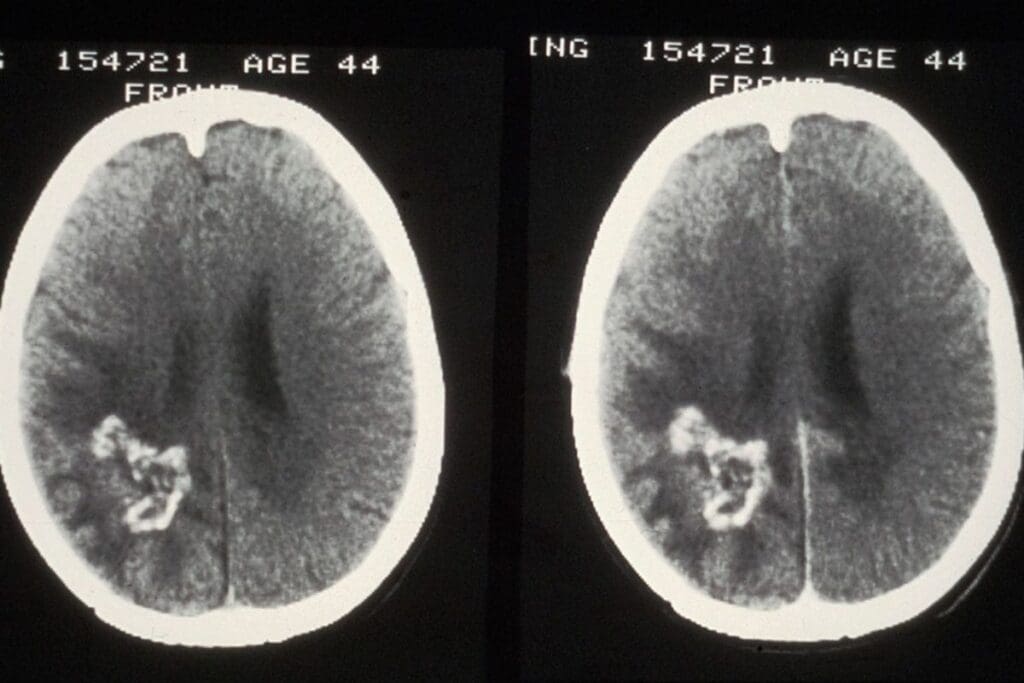

Unenhanced Phase: Baseline Imaging

The first phase is the unenhanced phase. Here, images are taken without contrast. It shows the urinary tract’s baseline, helping spot stones or other issues.

Baseline imaging is key. It lets radiologists see the urinary tract as it is naturally. This helps them compare it with the later phases.